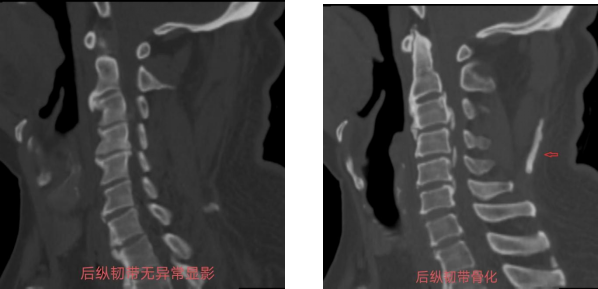

这病比颈椎病更可怕,脊柱的后纵韧带发生异位骨化,会让本该柔软的后纵韧带悄悄“石化”,像钢筋一样压迫脊髓和神经,出现的症状远比普通颈椎病凶险。

当之无愧的“金标准”,据日本多中心研究(2016)和《Eur Spine J》(2020)文献证实,薄层CT对韧带“石化”的检出率达98%-100%,病理符合率94%,能精准锁定病灶。